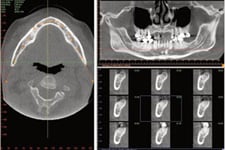

We have the latest, and most advanced 3-D Imaging technology in our new state of the art facility. Three dimensional imaging for dental implant placement provides for precise diagnosis and control of implant placement. In many cases, Dr. Gould will recommend a 3-D scan (also known as a Cone Beam Computed Tomography scan) to facilitate precise treatment planning of your dental implant.

We have the latest, and most advanced 3-D Imaging technology in our new state of the art facility. Three dimensional imaging for dental implant placement provides for precise diagnosis and control of implant placement. In many cases, Dr. Gould will recommend a 3-D scan (also known as a Cone Beam Computed Tomography scan) to facilitate precise treatment planning of your dental implant.

Dr. Gould can virtually plan your dental implant on the computer to ensure ideal placement and esthetics. We can then utilize your virtual plan to place your implant using guided surgery. Ask us about our 3-D Implant Imaging capabilities!

Dr. Gould can virtually plan your dental implant on the computer to ensure ideal placement and esthetics. We can then utilize your virtual plan to place your implant using guided surgery. Ask us about our 3-D Implant Imaging capabilities!